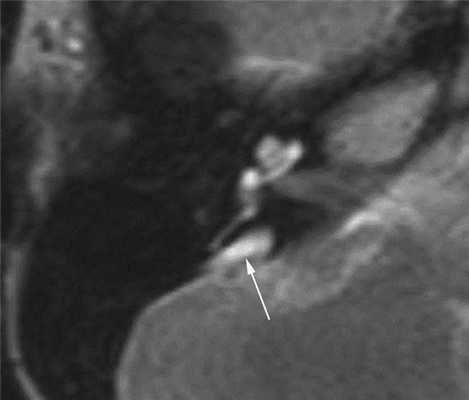

При наличии сенсоневральных нарушений слуха неясной этиологии показано выполнение МРТ головного мозга и пирамид височных костей. Т2-взвешенные изображения позволяют отчетливо выявить расширенный водопровод преддверия (рис. 3).

Рис. 3. Широкий водопровод преддверия (стрелка). Магнитно-резонансная томограмма правой височной кости в аксиальной проекции. Пациент А., 14 лет.